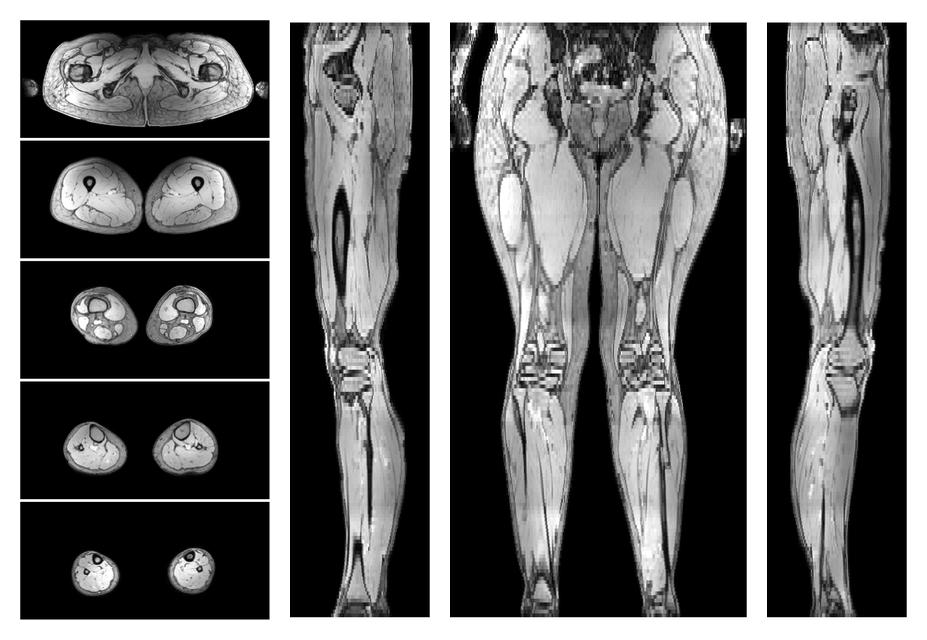

Muscle segmentation

Convolution neural network based (UNET) fiber automated muscle segmentation, for information look here».

• Automated muscle and bone segmentation.

Overlay of automated muscle segmentation labels on dixon water image.